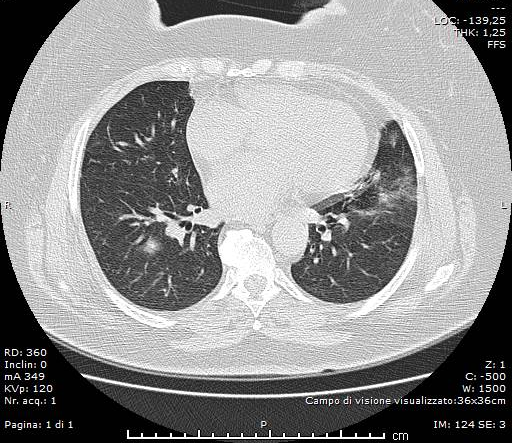

Si esegue d’urgenza, a completamento diagnostico, indagine TC del Torace in condizioni basali ed algoritmo ad alta risoluzione (HRCT), con scanner a 64 strati, le cui immagini ottenute sono state analizzate con slice-thickness di 1,2 mm e successive ricostruzioni MPR (assiali, sagittali e coronali).

HRCT ha documentato, in entrambi i parenchimi polmonari, la presenza di plurimi addensamenti con aspetto “a vetro smerigliato” ed alcune aree con pattern “crazy-paving”, per la coesistenza di aree “ground-glass”, di consolidamento ed ispessimento interstiziali. Trachea e bronchi pervi. Qualche piccolo linfonodo, reattivo, in sede ilo-mediastinica. Immagine cardiaca nei limiti. Non evidenza di versamento pericardico. Minimo versamento pleurico basale bilaterale.

La TC ha messo bene in evidenza, inoltre, il “segno ragnatela” (“spider web sign”), rappresentato da un’area di opacità ground-glass, ad aspetto grossolanamente triangolare ed angolare, in sede basale sub-pleurica a destra, con all’interno setti interlobulari ispessiti come una rete; la pleura adiacente era stirata ed ispessita, denotando una forma simile a quella di una ragnatela nell’angolo.

Al settimo giorno di terapia il paziente mostrava un modesto, ma progressivo, miglioramento del quadro clinico e laboratoristico, con discreta diminuzione dei valori di PCR, LDH; stabile la leucopenia. In decima giornata viene ripetuta l’indagine HRCT, per rivalutare il quadro radiologico, che ha documentato, in entrambi i polmoni, una riduzione sia degli addensamenti parenchimali con aspetto “a vetro smerigliato”, che delle aree con pattern “crazy-paving”, che tuttavia erano comunque ancora presenti nei campi medi ed in sede periferica, bilateralmente. Persisteva ancora l’ispessimento/stiramento della pleura viscerale in sede basale posteriore destra, dalla quale si dipartivano setti e tralci ad aspetto fibrosclerotico. Non era più visibile il versamento pleurico.